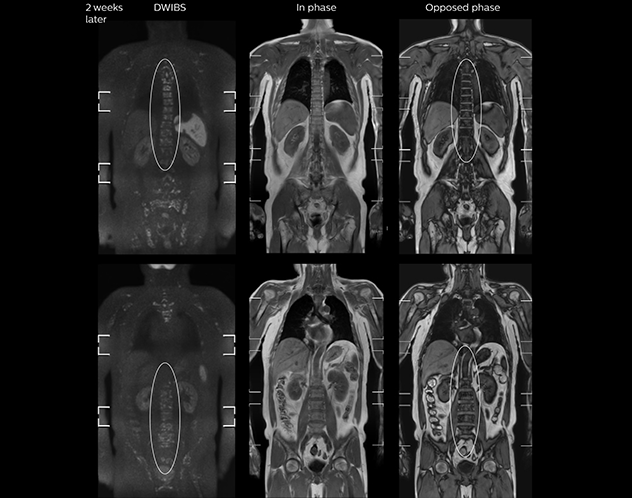

“Once Ingenia was available, our first goal was to shorten the exam time of our scan,” says Mr. Naka. The next goal was to create a protocol that provided more clinical information.

“When we limited the scan coverage to the area from neck to femur, we could fit more clinical information in approximately the same scan time. So, we added coronal mDIXON, sagittal T1-weighted, and sagittal STIR sequences to our examination, instead of performing only axial DWIBS and coronal single-shot TSE scans.”

The single shot T2-weighted TSE images are used for morphology and compared to DWIBS images to identify T2 shine-through. Sagittal STIR images are used in patients with inflammation or bone metastasis.

“With coronal DWIBS, we can perform a full whole body exam, including other sequences, within 30 min.”

“When we use a coronal DWIBS acquisition, we can perform a full whole body examination, including other required sequences, within 30 minutes,” he says.

“This is considerably faster than the previously used exam with axial whole body DWI, which took more than 45 minutes,” he notes. “A shorter exam is more patient-friendly and allows us to also use it on patients in poor health who would have difficulty tolerating a long exam. Limiting the exam time is also helpful for scheduling, because it fits in a normal single exam timeslot.”